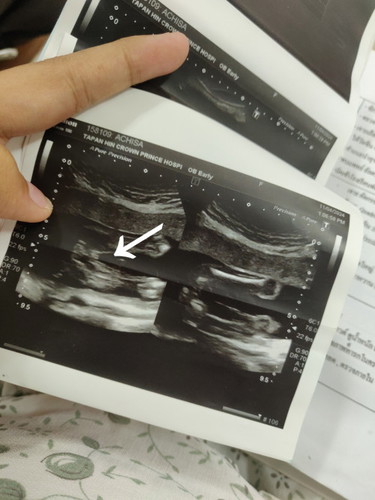

เดาว่าน่าจะผู้ชายค่ะแม่เพราะมีจู๋ยื่นออกมา หมอที่ซาวด์ให้เคยบอกว่าผู้หญิงจะเห็นเป็นกรีบส่วนผู้ชายจะเป็นไข่และมีจู๋ยื่นออกมาค่ะ

แม่เห็นเป็นกลีบ แม่ว่าผู้หญิงค่ะ เพราะแม่ก็ได้กลีบลูกสาวเหมือนกันค่ะ

เดาว่าชายจ้า เหมือนมีจุ๊ดจู๋ยื่นออกมาอยู่นะแม่

เหมือนผู้หญิงเลยคะเหมือนเป็นกลีบๆ

เห็น2กลีบค่ะแต่อยากให้ชัวร์ต้อง20วีค